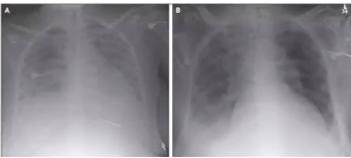

胸部X线片:两肺透光度减低,重力依赖性肺不张,病变不均一性,不能用渗出、小叶/肺不张或结节解释;

图1 ARDS胸部X片[2]呼吸衰竭不能完全用心力衰竭或液体负荷解释;